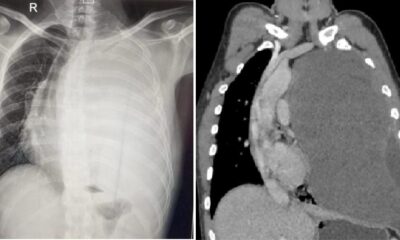

सफलता: फेफड़े में था सवा तीन किलो का ट्यूमर, एम्स के चिकित्सकों ने बचाई जान…

June 21, 2024ऋषिकेश। समय पर इलाज शुरू होने से गम्भीर बीमारी से ग्रस्त व्यक्ति के जीवन को भी...